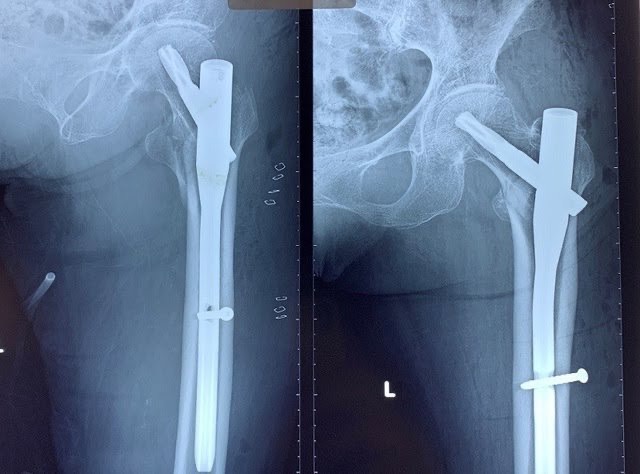

4.2. Điều trị phẫu thuật: Nếu không được điều trị phẫu thuật kịp thời bệnh nhân sẽ có những biến chứng nặng nề như: viêm phổi, viêm đường tiết niệu, đặc biệt gây loét các điểm tỳ và bệnh nhân sẽ tử vong do những biến chứng đó. Có nhiều chỉ định phẫu thuật khác nhau được đặt ra cho gãy LMC ở người cao tuổi như kết hợp xương ( đóng đinh nội tủy, nẹp DHS …), thay khớp háng. Mỗi phương án phẫu thuật có những ưu nhược điểm khác nhau. Đối với các loại gãy LMC di lệch phân độ A2.2 và A2.3 ( theo Muller), gãy xương kèm theo tình trạng thoái hóa khớp háng từ trước hoặc chất lượng xương yếu do loãng xương không đủ độ chắc để có thể giữ vững được các phương tiện kết hợp xương bên trong hoặc trong trường hợp đã điều trị thất bại đối với các phương pháp kết hợp xương trước đó thì chỉ định thay khớp háng nhân tạo cho bệnh nhân cũng là một giải pháp tốt.